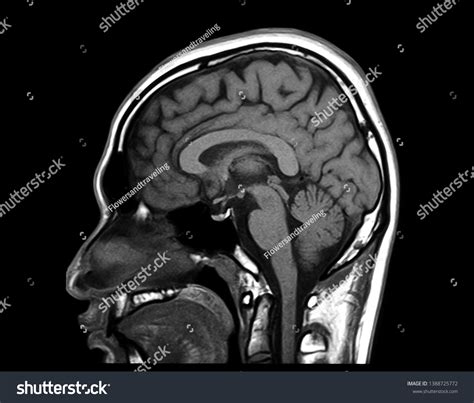

Medical imaging technology has revolutionized the way we understand human health, and among these diagnostic tools, Brain MRI Images stand out as the gold standard for visualizing the complex architecture of the central nervous system. Magnetic Resonance Imaging (MRI) provides incredibly detailed, non-invasive views of the brain's internal structures, allowing medical professionals to identify anomalies, track the progression of diseases, and plan surgical interventions with pinpoint accuracy. Unlike X-rays or CT scans, which rely on ionizing radiation, MRI machines utilize powerful magnetic fields and radio waves to generate sophisticated, multi-planar cross-sections of brain tissue.

At its core, the process of capturing Brain MRI Images is a marvel of physics and engineering. When a patient enters the scanner, their body interacts with a strong magnetic field that causes the hydrogen protons in their body’s water molecules to align. Radiofrequency pulses are then applied, forcing these protons to shift their alignment. As the pulses are turned off, the protons return to their natural state, emitting radio signals that the MRI scanner detects and converts into high-resolution imagery.

This technology is essential for distinguishing between various types of tissues, such as gray matter, white matter, and cerebrospinal fluid. By manipulating the timing of the radiofrequency pulses—a process referred to as adjusting pulse sequences—radiologists can emphasize different pathological features, making it easier to spot tumors, lesions, or inflammatory processes.

Once the images are acquired, they are processed and sent to a radiologist. These specialists are trained to meticulously examine the Brain MRI Images, looking for subtle deviations from normal anatomy. They look for signals that are “hyperintense” (bright) or “hypointense” (dark) on the scan, which often indicate different types of pathology. The radiologist then synthesizes these findings into a comprehensive report for the referring physician, who uses the data to determine the next steps in treatment or management.